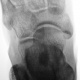

Травма.  Пациент направлен на рентгенографию стопы

P.S. похоже на костный островок

Не заметила ничего травматического...

Участок склероза или остеопойкилия.